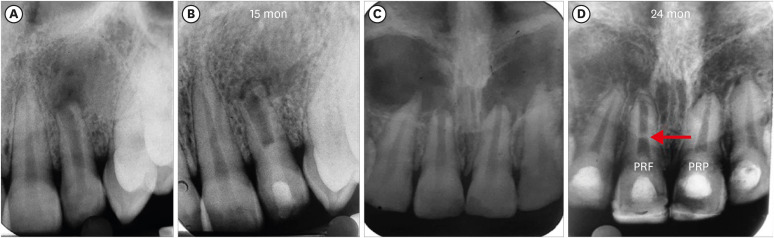

5. Intracanal calcification (ICC)

ICC occurring in the root canal space anywhere between capping material and apical foramen was evident in a total of 22 teeth. It was seen more frequently in the BC group (9 teeth: 75%) than in the PRP and PRF groups, in which the number of teeth involved was 7 and 6, respectively (Figure 4). Calcification was seen in the apical third in 13 teeth, in the middle third in 7 teeth, and in the coronal third of the canal in 2 teeth. It took the form of diffuse deposits in 15 teeth; however, 5 teeth showed calcific bridge-like deposits running from the mesial to the distal canal wall. Nonetheless, the statistical analysis revealed no significant difference in the occurrence of ICC among the 3 groups (p = 0.68) (Table 3).

Figure 4

Intracanal calcification. (A, B) No. 2 of the blood clot group: apical one-third. (C, D) No. 3 of the platelet-rich plasma group: apical one-third. (E, F) No. 7 of the platelet-rich fibrin group: coronal one-third close to Biodentine.

Figure 10 represents occurrence of ICC in each group. ICC was seen in 25 teeth, with the highest frequency in the BC group (11: 91.67%), followed by the PRP group (8: 66.667%) and the PRF group (6: 54.55%) (Supplementary Table 1, Table 4). The presence of ICC was also significantly greater in immature than in mature teeth. This observation was seen in both IOPAR (p = 0.015) and CBCT (p = 0.003) observations (Table 5).

Intracanal calcification. (A) No. 6 in the blood clot group: discernible on cone-beam computed tomography only, (B) No. 3: platelet-rich plasma group: diffuse in nature, (C) No. 7: platelet-rich fibrin group: calcific bridge apical to Biodentine.

In the present study, CBCT detected ICC in more teeth than IOAPR, as both sagittal and coronal sections could be analyzed for any opacities within the root canal space indicating ICC, and its incidence was higher in immature teeth. The literature on trauma also supports this finding [29]. The higher incidence of ICC in the present study may be due to the compound effect of the use of calcium hydroxide as an intracanal medicament, along with the other contributing factors, as revascularization-associated intracanal calcification (RAIC) was reported to be present in 76.9% in cases medicated with calcium hydroxide, constituting a higher percentage than was observed when antibiotic paste was used (46.2%) in the study of Song et al. [30]. ICC occurred more frequently in the BC group than in the groups using platelet concentrates, as inducing bleeding from the periapex may carry periodontal ligament stem cells and bone marrow stem cells from the alveolar bone, thereby recruiting cells with cementogenic and osteogenic differentiation capacities into the root canal space, leading to ectopic cementum and bone formation inside the lumen of the root canal [31,32]. As in the present study, Song et al. [30] also reported that RAIC was more prevalent when bleeding was induced in the canal (69.6%) than in cases without bleeding (33.4%). Ulusoy et al. [1] also reported a lower risk of ICC when platelet concentrates were used. However, ICC did also occur in cases where platelet concentrates were used, as all these scaffolds have the same source of growth factors (i.e., platelets). This could suggest the possibility that the current REP protocols and blood/blood-derived scaffolds recruit osteogenic and cementogenic cells into the root canal. Pulp hemorrhage after trauma can also become a nidus for calcification and lead to narrowing of the pulp canal space [33]. Additionally, ICC may be related to the osteoinductive activity of calcium silicate materials [34]. The incidence of the calcific bridge just below Biodentine was also seen in a few cases in the present study; however, these calcifications were seen in all groups. Thus, an analysis of the results of the present study confirmed the null hypothesis.